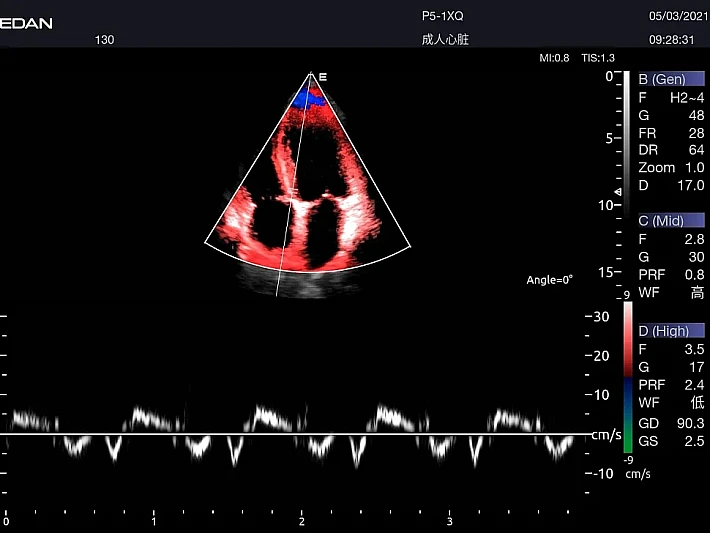

Медицинское оборудование и сервисное обслуживание